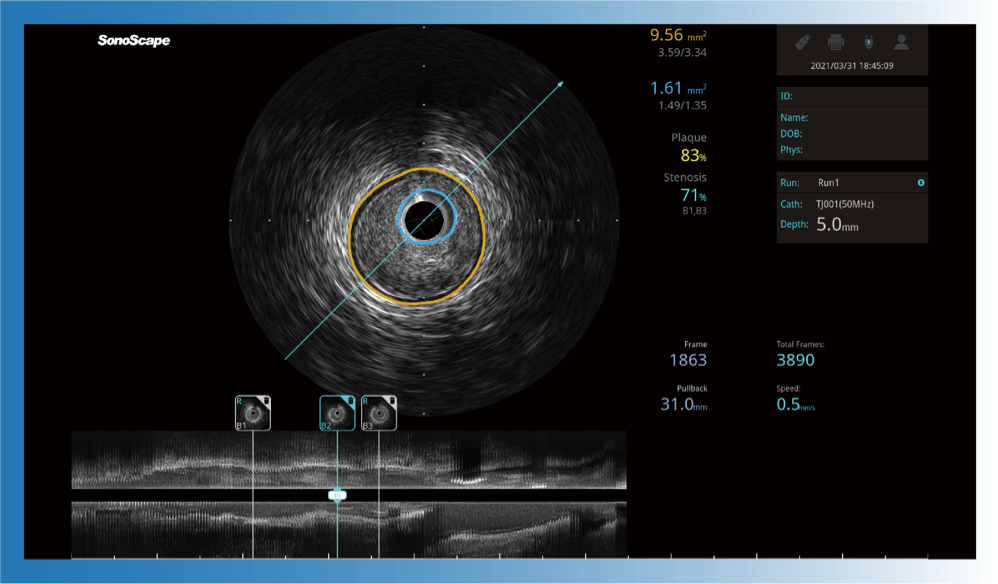

对比传统IVUS导管成像,竞技宝(JJB)官方网站宽频IVUS图像的近场支架梁显影更细腻,远场中膜外血管仍清晰可辨,兼顾远中近,兼顾分辨力与穿透深度

一键智能描迹,自动测量斑块负荷、面积狭窄率等指标,准确率高于90%